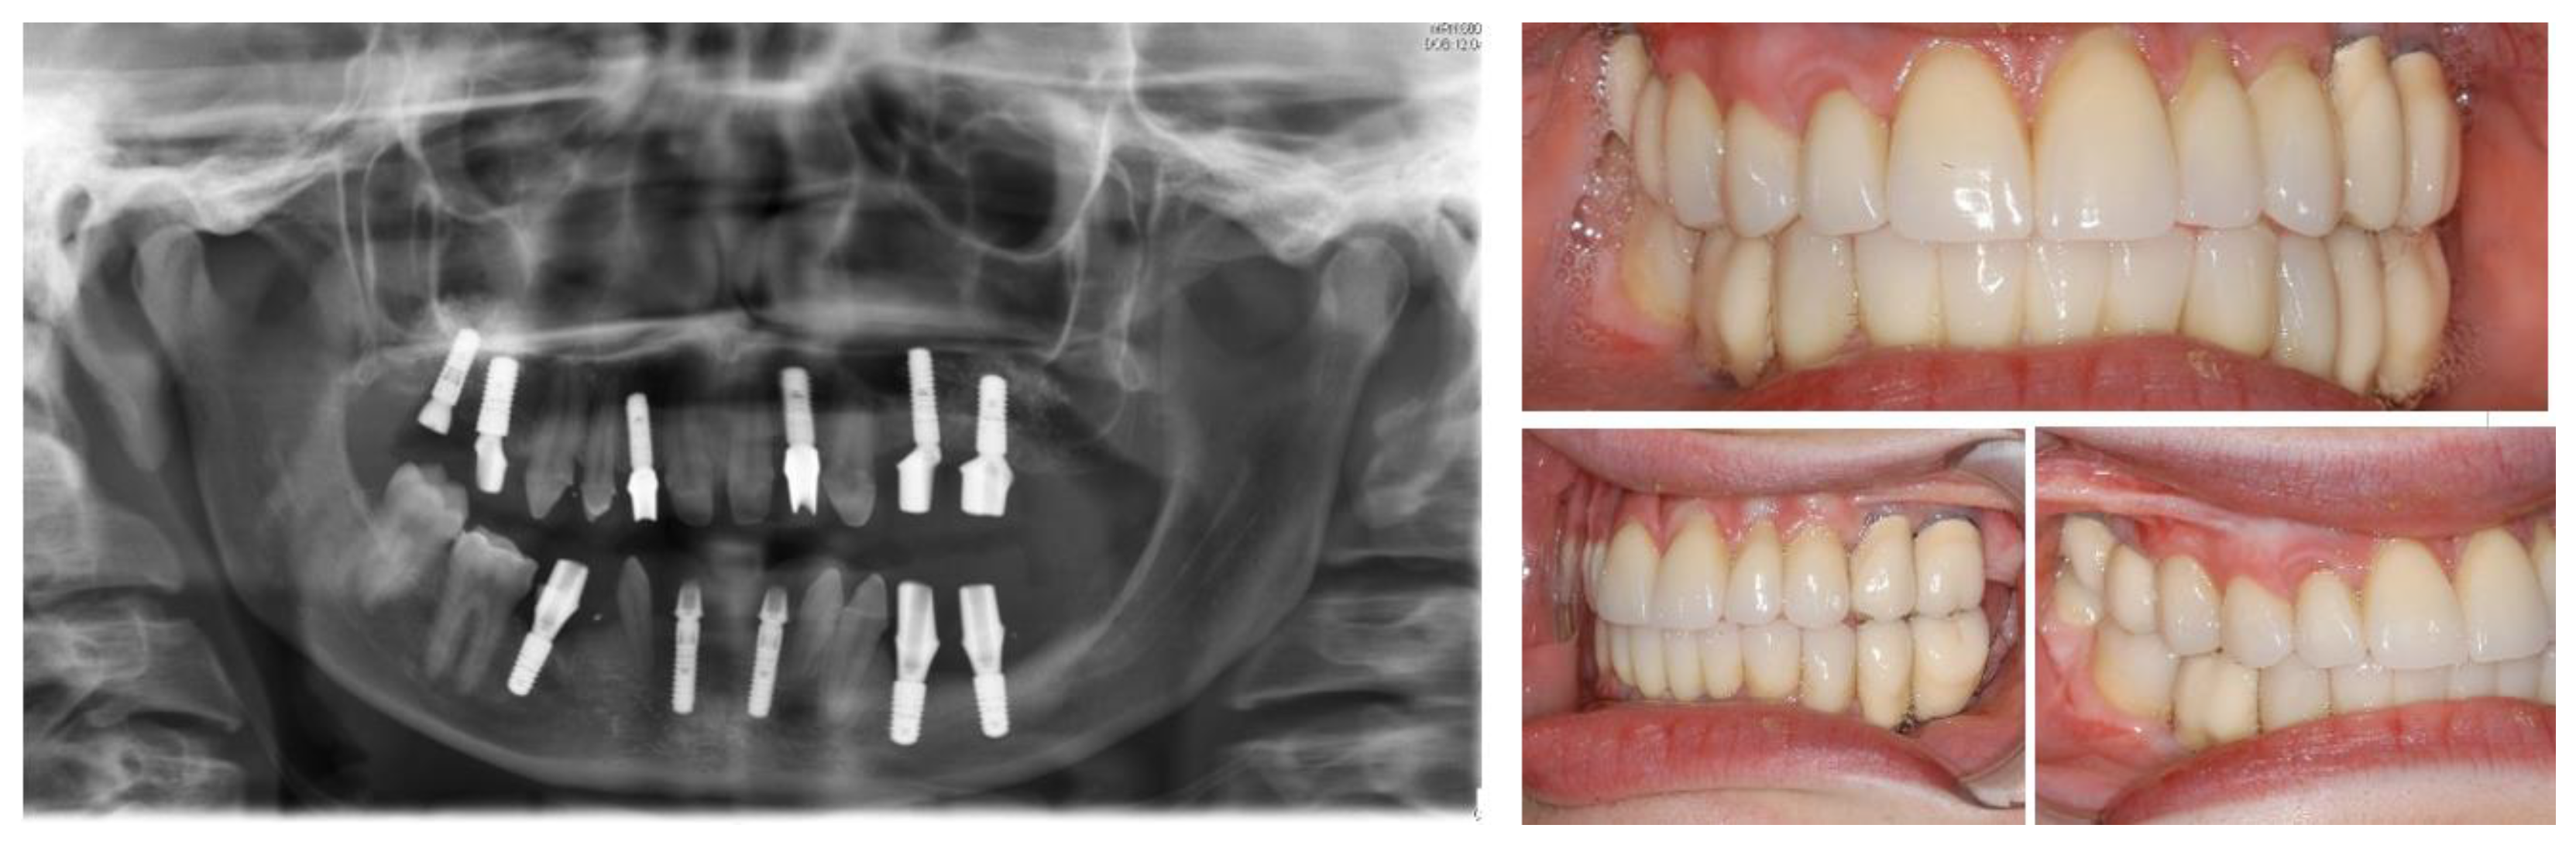

2.1. Case One